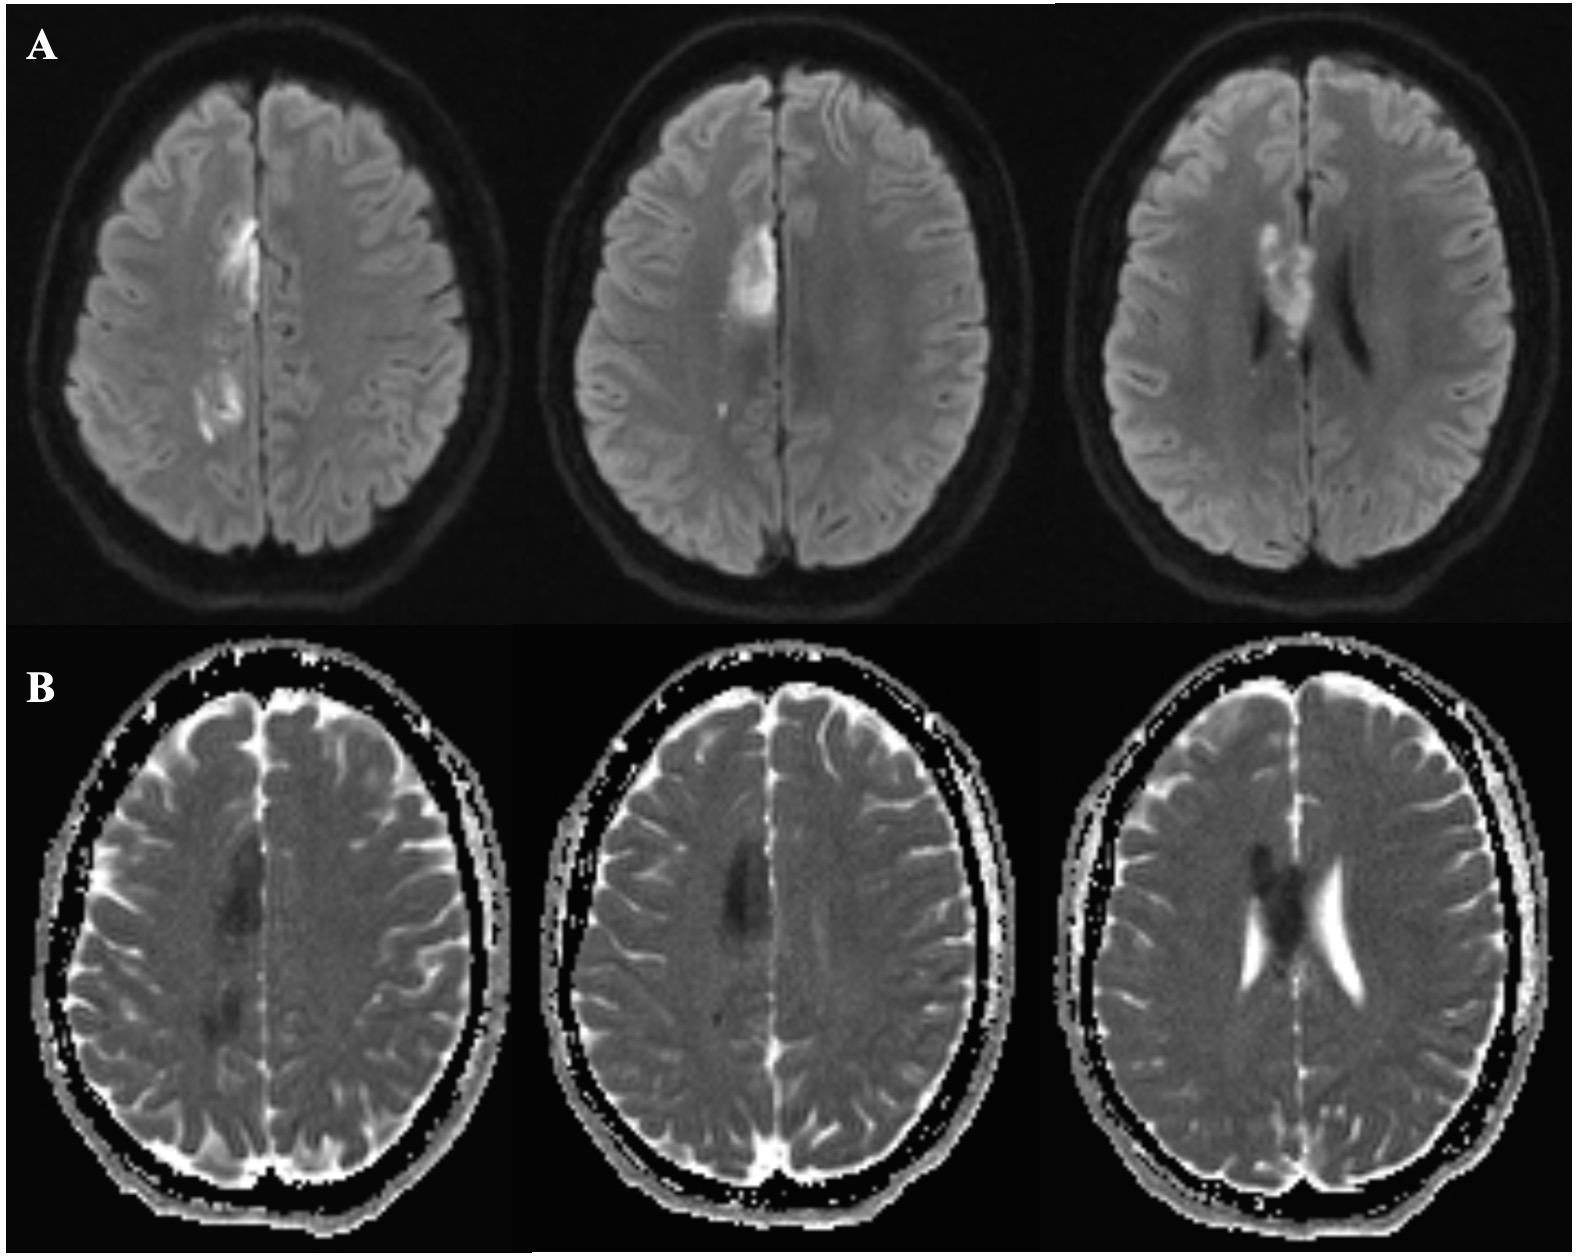

Results: Brain MRI showed acute ischemic infarct in the distal right anterior cerebral artery (ACA) territory involving the right cingulate gyrus, corpus callosum and scattered paramedian frontoparietal infarct (Figure 1). MRA head and neck with contrast were unremarkable. Angiogram showed a subocclusive thrombus at the origin of the right callosomarginal artery, which corresponds to the area of infarct noted on MRI and likely represented in situ thrombosis as opposed to proximal embolic source. Patent foramen ovale (PFO) was confirmed on transthoracic echocardiogram (TTE) and negative duplex ultrasound for deep venous thrombosis. The hypercoagulable work up was pending and the patient was on the dual antiplatelet therapy. She gradually gained normal control of her left hand over the next 48 hours even though there was still the residual left side weakness.

Figure 1: Brain MRI